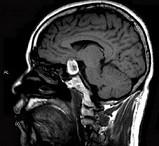

问题 男性,55岁,头痛一年余,两个小时前突然出现剧烈头痛,MRI检查如图所示,最可能的诊断为()

选项 A.垂体瘤 B.脑膜瘤 C.颅咽管瘤 D.垂体瘤并卒中 E.动脉瘤

答案 D